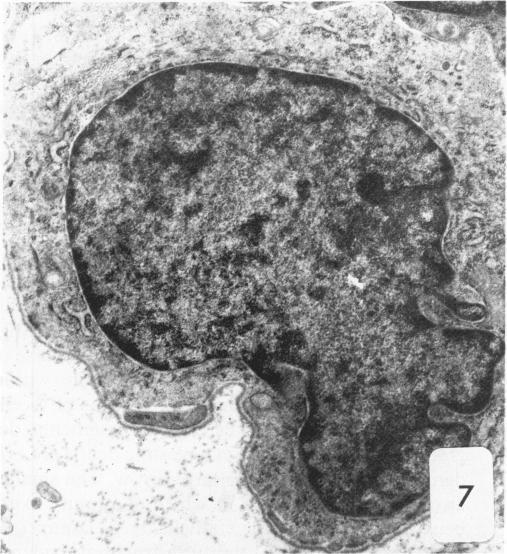

Dunning R3327-H rat prostate adenocarcinoma cells, when grown in syngeneic (Copenhagen) rats or nude mice, produce tumors with prominent hypercellular stroma. The authors have previously demonstrated the presence of anomalous steroid-sensitive cells in both the epithelium and stromal compartments of this model system. In order to better understand the histogenesis of these cells, the authors studied samples of the tumor which were radiolabeled overnight with tritiated dihydrotestosterone (3H-DHT). Frozen sections of the tissues were thaw-mounted onto autoradiographic emulsion-coated slides to permit silver grain identification in association with nuclei of androgen-sensitive cells. Surprisingly, numerous silver grains were found to be associated with nuclei of large cells within the stroma. Therefore, these cells were termed "epithelioid" pending confirmation of their origin. To further define these cells and their relationship to the surrounding matrix, autoradiograms have now been examined immunohistochemically with antibodies directed against the basement membrane glycoprotein, laminin, as well as antibodies specific for intermediate cytoskeletal filaments. Following identification of acinar basement membranes, epithelioid cells were identifiable both in the stroma and in the acinar epithelial cell layer. Histochemical staining with acid phosphatase, a marker for prostatic epithelium, was performed and shown to be present in acinar epithelial cells as well as in epithelioid cells. Additionally, fluorescence-activated cell sorting was employed to characterize the DNA content of cell types within the H tumor. Epithelioid cells were found to be in highest concentration in an aneuploid peak with a ploidy of approximately 6N. The autoradiographic, immunohistochemical, cytometric, and ultramicroscopic studies suggest that 1) epithelioid cells are epithelial derived stromal cells; 2) these epithelioid cells arise by pathologic division of aneuploid neoplastic precursor cells of approximately 3N ploidy, which are found within the prostatic epithelium; and 3) the resulting 6N cells degrade the basement membrane locally, invade the stroma, and populate it. Here, they can be distinguished from fibroblasts by their size, acid phosphatase activity, and hormone receptor content. Thus, the term "epithelioid" is inappropriate; and these cells should be regarded simply as large neoplastic epithelial (LNE) cells. The presence of this cell type suggests that this tumor subline represents a useful naturally occurring model for the study of the initial stages of neoplastic transformation.

邓宁R3327 - H大鼠前列腺腺癌细胞在同基因(哥本哈根)大鼠或裸鼠体内生长时,会产生具有显著细胞增多性基质的肿瘤。作者此前已证明在该模型系统的上皮和基质区室中均存在异常的类固醇敏感细胞。为了更好地理解这些细胞的组织发生,作者研究了用氚化双氢睾酮(3H - DHT)过夜进行放射性标记的肿瘤样本。将组织的冰冻切片解冻后贴在涂有放射自显影乳剂的载玻片上,以便确定与雄激素敏感细胞核相关的银颗粒。令人惊讶的是,发现大量银颗粒与基质内大细胞的核相关。因此,在确认其起源之前,这些细胞被称为“上皮样细胞”。为了进一步定义这些细胞及其与周围基质的关系,现在已用针对基底膜糖蛋白层粘连蛋白的抗体以及针对中间细胞骨架丝的特异性抗体对放射自显影片进行免疫组织化学检查。在确定腺泡基底膜后,在上皮样细胞的基质和腺泡上皮细胞层中均可识别出上皮样细胞。用酸性磷酸酶进行组织化学染色,酸性磷酸酶是前列腺上皮的标志物,结果显示其存在于腺泡上皮细胞以及上皮样细胞中。此外,采用荧光激活细胞分选技术来表征H肿瘤内细胞类型的DNA含量。发现上皮样细胞在非整倍体峰中浓度最高,其倍性约为6N。放射自显影、免疫组织化学、细胞计量学和超微结构研究表明:1)上皮样细胞是上皮来源的基质细胞;2)这些上皮样细胞由前列腺上皮内约3N倍性的非整倍体肿瘤前体细胞的病理性分裂产生;3)产生的6N细胞局部降解基底膜,侵入基质并在其中聚集。在这里,它们可以通过大小、酸性磷酸酶活性和激素受体含量与成纤维细胞区分开来。因此,“上皮样”这个术语并不恰当;这些细胞应简单地视为大肿瘤上皮(LNE)细胞。这种细胞类型的存在表明该肿瘤亚系是研究肿瘤转化初始阶段的一个有用的自然发生模型。